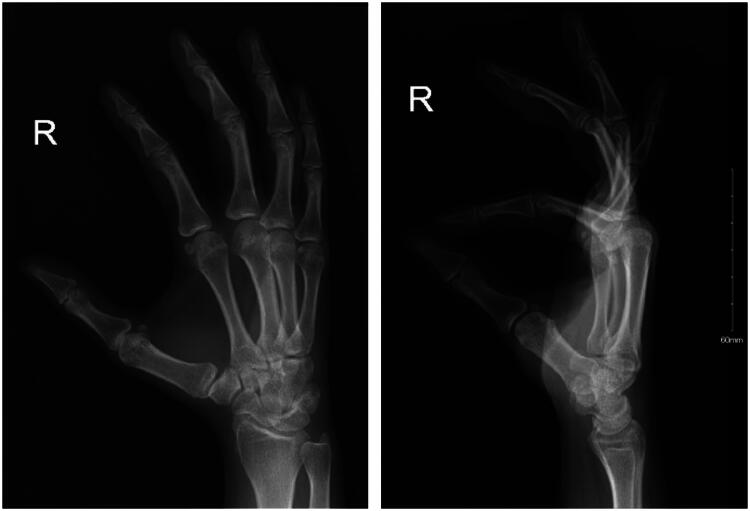

马松瘤,或血管内乳头状内皮增生(IPEH),是一种罕见的良性血管病变,可以模仿其他软组织肿瘤。我们报告一个33岁女性的病例,她有一个疼痛的数字肿块。手术证实IPEH。文献回顾确定了8例类似病例,突出了其罕见性和诊断挑战。

Masson's tumor, or intravascular papillary endothelial hyperplasia (IPEH), is a rare benign vascular lesion that can mimic other soft-tissue tumors. We present a case of a 33-year-old woman with a painful digital mass. Excision confirmed IPEH. Literature review identified eight similar cases, highlighting its rarity and diagnostic challenge.